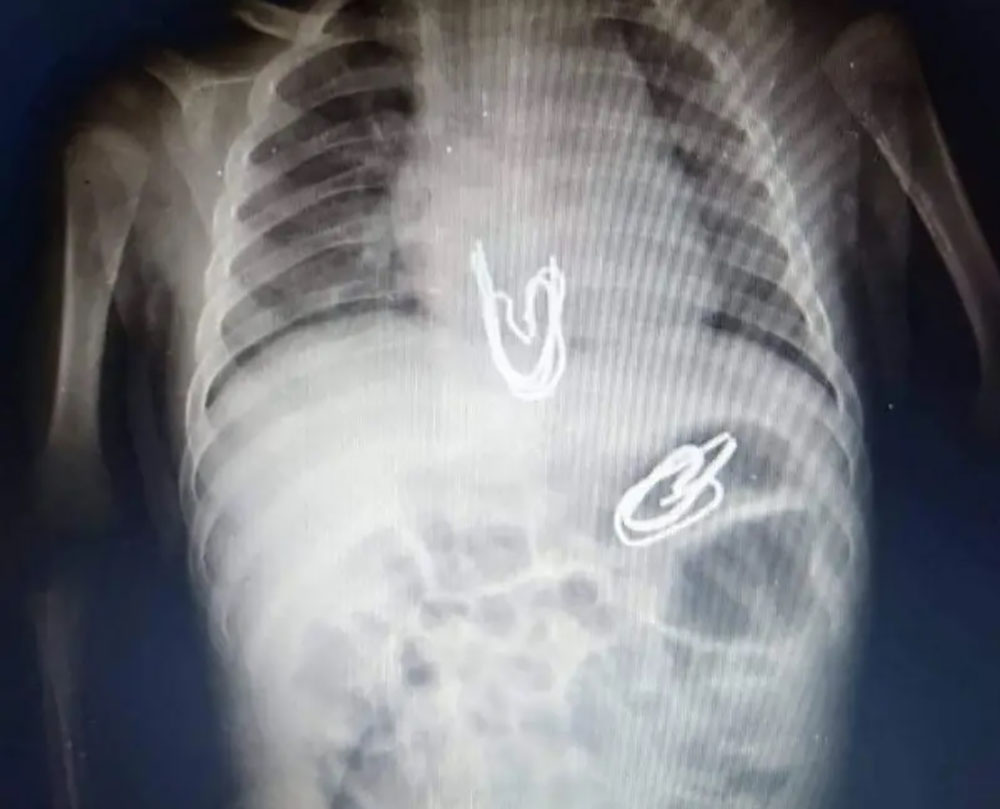

وبعد اجراء أشعة لبطن الطفل تبين وجود مجموعة من هذه المشابك المعدنية في المريء وأخرى في المعدة، ولأن هذه الدبابيس ذات أطراف حادة فكان هناك تخوف من أن تكون قد جرحت جدار المعدة والمريء، وهو ما دفع الفريق الطبي لعمل أشعة مقطعية أثبتت عدم وجود جروح في جدار المعدة والمريء.